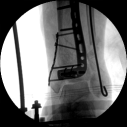

3.在脛骨近端穿入一根克氏針,連接CO外固定架進行固定,并外踝處穿入一根克氏針進行固定。C臂透視位置滿意,縫合結束手術。